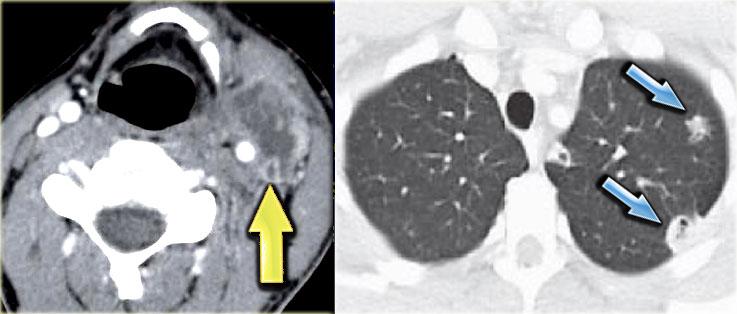

Huyết khối tĩnh mạch cảnh

Huyết khối tĩnh mạch cảnh trong là một tình trạng thường bị chẩn đoán thiếu, có thể xảy ra như một biến chứng của nhiễm trùng vùng đầu cổ, phẫu thuật, đặt catheter tĩnh mạch trung tâm và lạm dụng thuốc tiêm tĩnh mạch.

Huyết khối tĩnh mạch cảnh bị nhiễm trùng do lan rộng từ nhiễm trùng hầu họng được gọi là hội chứng Lemierre.

Đây là một nhiễm trùng do vi khuẩn có thể gây ra bệnh suất nặng nề hoặc thậm chí tử vong, do cuối cùng các thuyên tắc nhiễm khuẩn có thể lan đến phổi.

Bên trái là hình ảnh một bệnh nhân đã được cắt thanh quản toàn phần vài năm trước.

Triệu chứng hiện tại là khối sưng đau ở bên trái cổ trong một ngày.

Bước 1

CT có tiêm thuốc cản quang tại mức giữa cổ cho thấy tân hầu họng với một số kẹp phẫu thuật ở bên trái và thùy tuyến giáp phải còn nguyên vẹn có ngấm thuốc.

Ngoài ra còn có một tổn thương giảm tỷ trọng hình tròn trong khoang cảnh bên trái.

Bước 2

Trong trường hợp này, việc phân tích các thành phần giải phẫu bình thường của khoang cảnh có thể ngắn gọn.

Khi so sánh bên trái với bên phải, rõ ràng chúng ta đang đối mặt với một tĩnh mạch cảnh trong bị giãn to và không ngấm thuốc.

Hình ảnh ở mức cao hơn cho thấy hình ảnh tương tự của tĩnh mạch cảnh trong (mũi tên).

Bước 3

Kết hợp với thông tin lâm sàng về khối sưng đau ở bên trái cổ, chỉ có một chẩn đoán duy nhất có thể:

Huyết khối cấp tính tĩnh mạch cảnh trong bên trái.

Hội chứng Lemierre

Khi chẩn đoán huyết khối cấp tính tĩnh mạch cảnh trong, hãy luôn tìm kiếm các triệu chứng phổi, tức là hội chứng Lemierre.